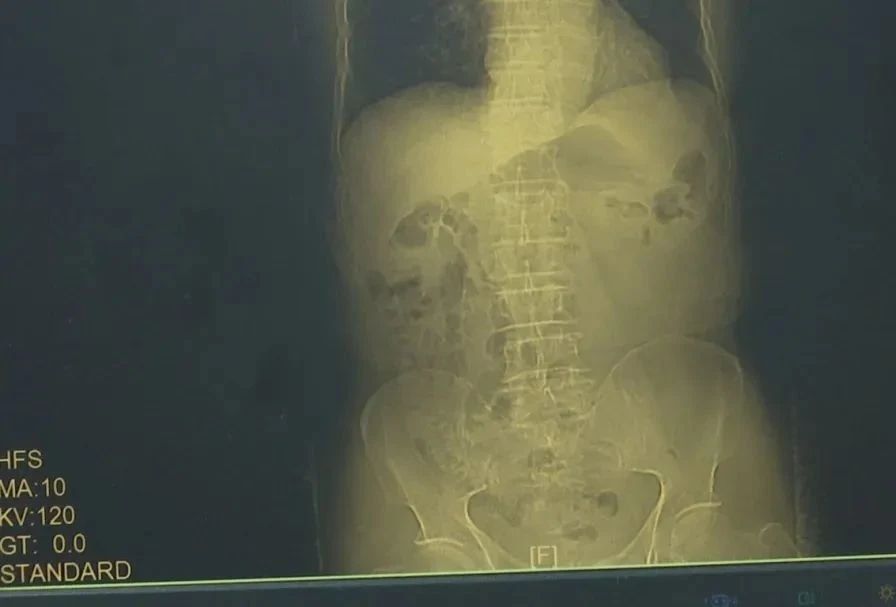

前去医院就诊被确诊为胃癌

也查出患有胃癌

两人癌症均处于早期

好在通过及时的手术,夫妇恢复状况良好,病理检查结果也传来佳音,愈后较为乐观。